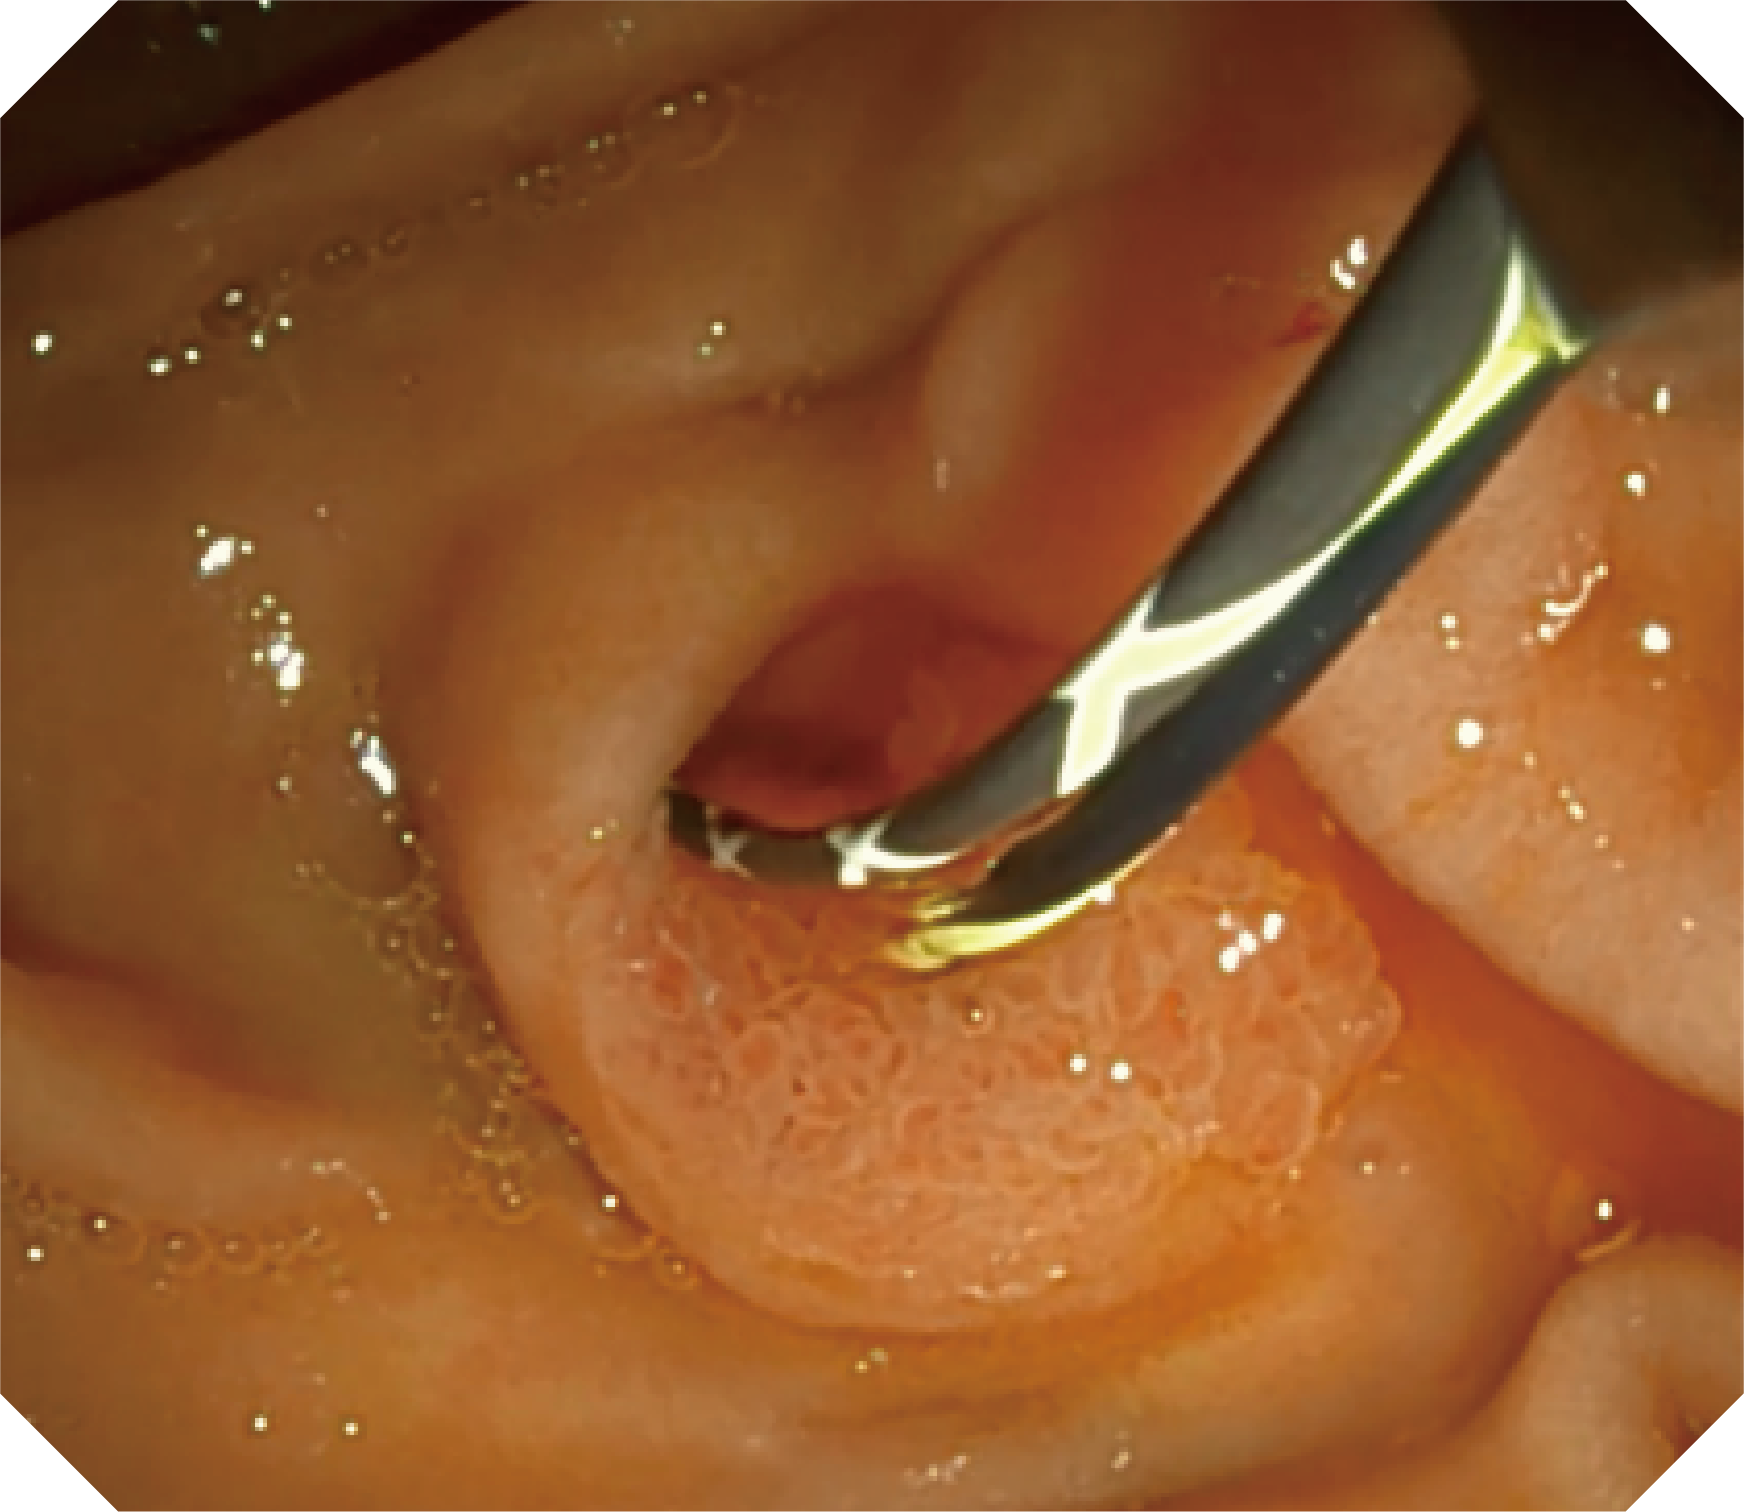

4.2mm大钳道,器械交换更顺畅

卓越的抬钳器控制

优异的手术器械抬举性